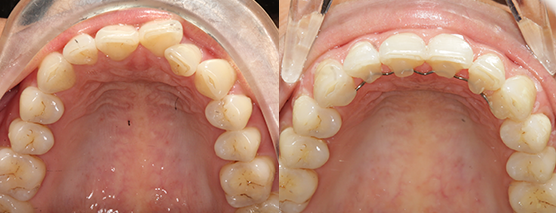

Case examples that can be treated in your practice.

(Cases treated by Dr Andrew Chang using in office aligner solutions)

Before

After